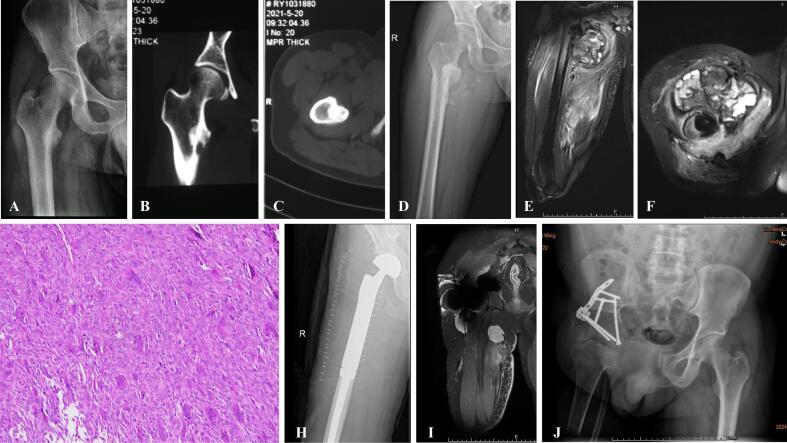

Of the 85 patients included, 27 cases underwent unplanned surgery at external hospitals, including 16 males and 11 females, with a median age of 44 years (range: 11-81 years). Initial preoperative radiologic findings in these patients undergoing unplanned surgery showed no periosteal reaction or soft tissue mass. No significant differences in OS, EFS, or LRR were observed between the unplanned and planned surgery groups (p > 0.05). However, MSTS scores were significantly lower in the unplanned surgery group (p < 0.001).

纳入的85例患者中,27例在外部医院接受了非计划性手术,其中男性16例,女性11例,中位年龄44岁(范围:11-81岁)。这些接受非计划性手术的患者术前最初的影像学检查结果显示无骨膜反应或软组织肿块。非计划性手术组和计划性手术组在OS、EFS或LRR方面未观察到显著差异(p>0.05)。然而,非计划性手术组的MSTS评分显著更低(p<0.001)。